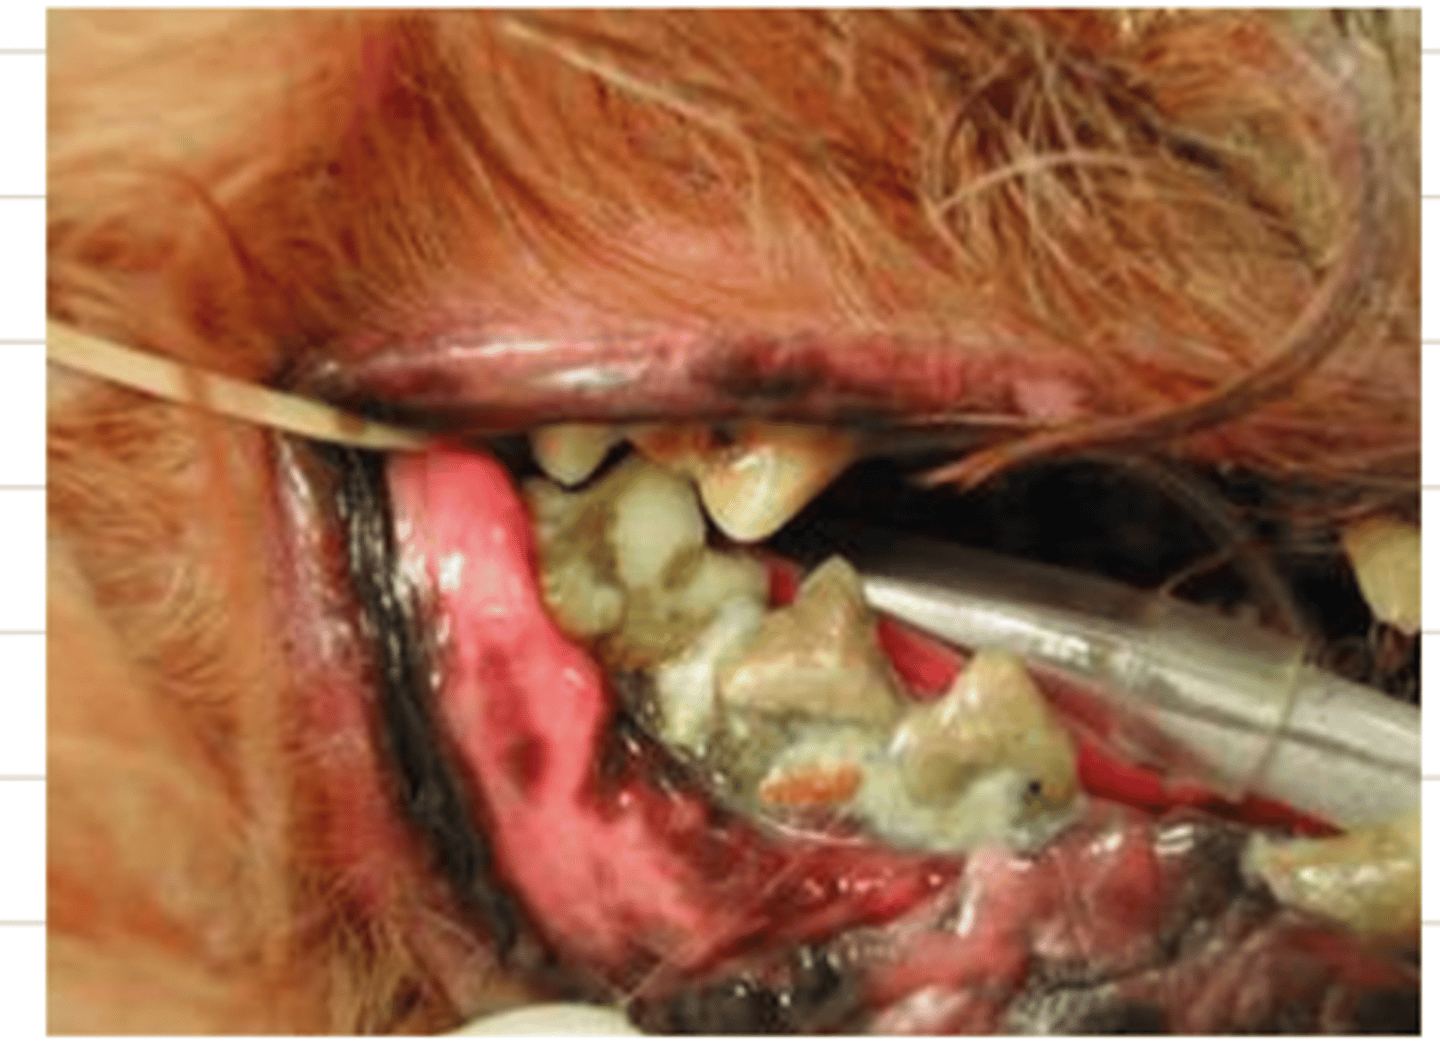

peridontal disease

what is this condition?

peridontal

this horse has ________ disease

peridontal disease

what is the problem here?